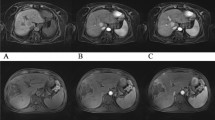

The difference in image quality between conventional and CS sequences was very slight but statistically significant (Table 3, p = 0.006 for reader 1 and p = 0.05 for reader 2). When analyzed sequence by sequence, no significant difference of image quality for both readers was found between CS and conventional images except for heart cine for reader 1. Globally, the agreement between readers for the evaluation of the conventional or the CS sequences was fair (κ = 0.30 and κ = 0.25 respectively). The presence of artifacts, and in particular motion artifact, is listed in Table 3. The latter was analyzed separately since one can hypothesize that CS sequences would be less prone to motion artifacts. Overall, the artifacts found by both readers can be classified as artifacts due to the presence of metal, suboptimal fat suppression, motion artifact (including respiratory artifacts), and noise and folding artifact. There was no difference in the occurrence of artifacts between conventional versus CS when all organs were pooled together but also when analyzed separately (except for 3D PD SPAIR for reader 2). The agreement between readers for the detection of artifacts was globally moderate (κ = 0.39 for conventional and κ = 0.47 for CS). When evaluated next to each other, the preferred sequence for each reader is reported in Table 4. Quantitative results such as CNR measured in conventional and CS sequences are shown in Fig. 1. Cardiac quantitative measurements performed on cine are shown in Table 5. The following results are described separately according to each organ. Figure 2 shows examples of images obtained for all evaluated applications.

Examples of images obtained with conventional (left) vs CS sequences (right) for all the applications tested, i.e. a Brain 3D T1 Gd (transverse reformat). b Brain 3D FLAIR (transverse reformat). c Heart cine. d Bile duct MRCP trig (maximum intensity projection). e Liver 3D T1 post Gd tra. f Liver 3D T1 post Gd cor. g Rectum 3D T2 VISTA (sagittal reformat). h Elbow 3D PD SPAIR. i Wrist 3D PD SPAIR. j Knee 3D PD SPAIR. The reformat orientation is shown for brain and rectum since it was the preferred orientation for interpretation

Liver contrast–enhanced 3D T1 transverse and coronal sequences

Reader 1 preferred the conventional sequence while reader 2 had most often no preference. Finally, diagnostic findings were identical except for one case for both readers and an additional case for reader 1 (in transverse orientation). Indeed, for one of the two patients, CS was acquired at a late phase after contrast medium injection which makes a comparison difficult for both readers. Reader 1 mentioned also too much respiration artifacts for interpretation of the CS sequence. Concerning the other patient, only reader 1 found a possible mild dilatation of intrahepatic bile ducts on conventional sequence that was not visible on CS, and mentioned that conventional sequence was prone to motion artifacts. Considering the other sequences of the exam, the ectasia was due to the artifacts and not real.